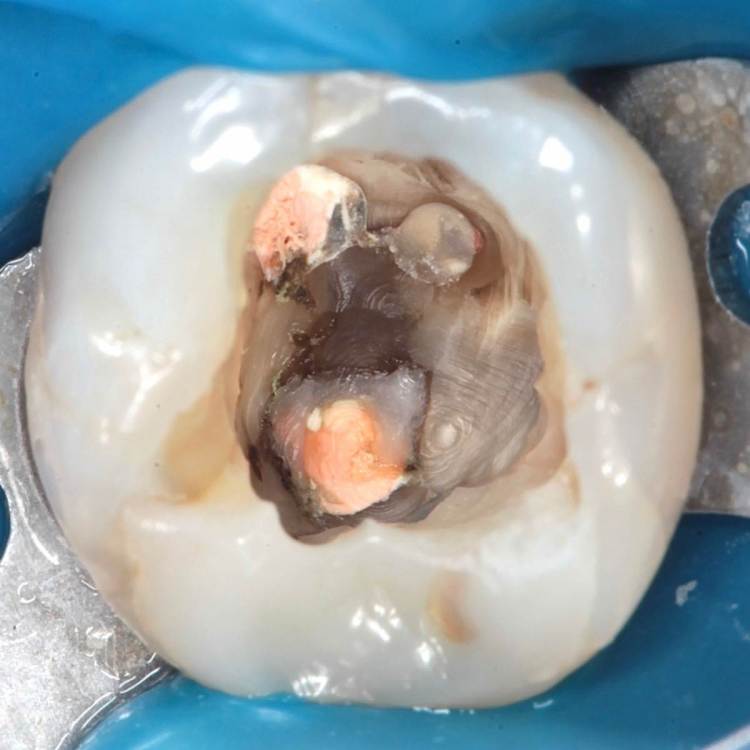

кальцием пафнуло дистально